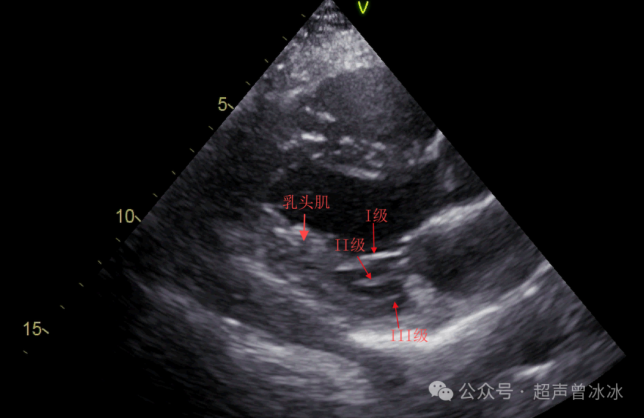

但按其部位和功能也确实分为三等:

I级腱索:起自乳头肌,远端附着于瓣叶边缘,主要防止瓣叶边缘外翻。

II级腱索:起自乳头肌,附着于瓣叶中部,加强对瓣叶的牵拉作用。

III级腱索:发自左室壁,附着于瓣叶基底部,固定瓣膜位置的作用,只位于后叶。

对应到超声图像就是↓

2379d9bb5cb76627c2bfa05e449e24dc3f9fd0cdb70bf77f97d7b58eed1f3ea0a5628596df3061a4

其中,I、II级腱索是腱索的核心成员,断了、冗长了容易引起二尖瓣关闭不全、脱垂甚至连枷。

III型腱索既细又短,切断III型腱索不影响瓣膜的功能。